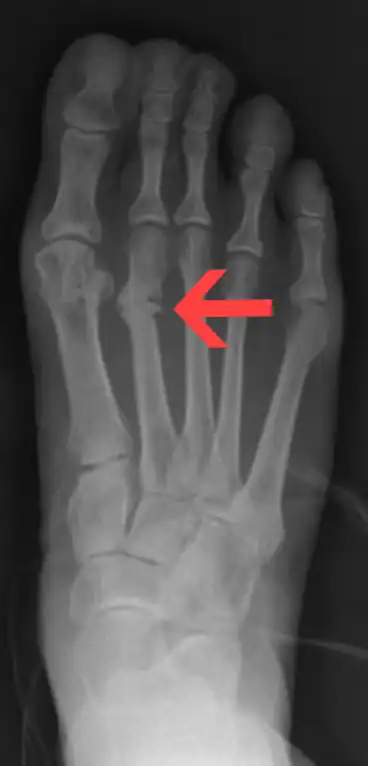

![]() | |

| Stress fracture of the second metatarsal bone | |